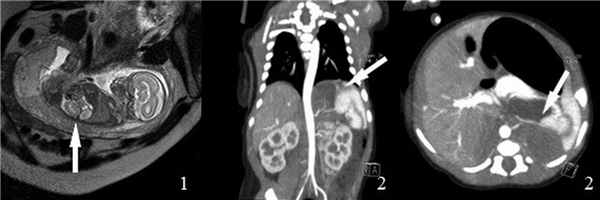

Выполнена мультиспиральная компьютерная томография органов грудной клетки и брюшной полости с внутривенным болюсным контрастированием: поддиафрагмально в парамедианных отделах слева определяется образование с преобладающим кистозным компонентом, общими размерами 51 × 21 × 37 мм, стенки и перегородки умеренно накапливают контрастный препарат. От аорты к образованию отходит мелкая артерия. Печень не увеличена. Контуры ровные, четкие (рис. 1).

Рис. 1. Магнитно-резонансная томограмма плода (а) и постнатальная мультиспиральная компьютерная томограмма органов грудной клетки (b) и брюшной полости (с) с внутривенным болюсным контрастированием с визуализацией образования, имеющего кистозно-солидную структуру и питающий сосуд, отходящий напрямую от аорты (обозначено белой стрелкой)

Fig. 1. Fetal MRI (а) and postnatal CT of chest (b) and abdomen (с) with contrast with visualization of mass that has a cystic-solid structure and a vessel that departs directly from the aorta (indicated by a white arrow)